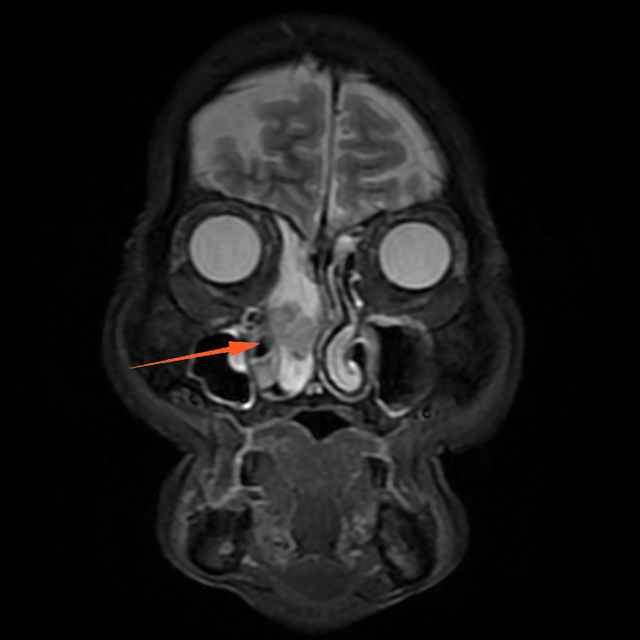

进一步增强MR显示:鼻腔右侧异常信号影,T1等信号,T2等高信号,DWI高信号,增强后周边强化为主。

蒋主任仔细阅读影像学图像,该患者的肿物在T2相有 “脑回征”,但又不典型,鼻窦骨质也没有明显的增生,肿物已经占满整个右侧额窦窦腔,好在患者额窦气化尚可,肿物未越过瞳孔中线,要彻底清除肿物,需要打开额窦,将窦内软组织完全清理干净并磨除基底部部分骨质再烧灼。